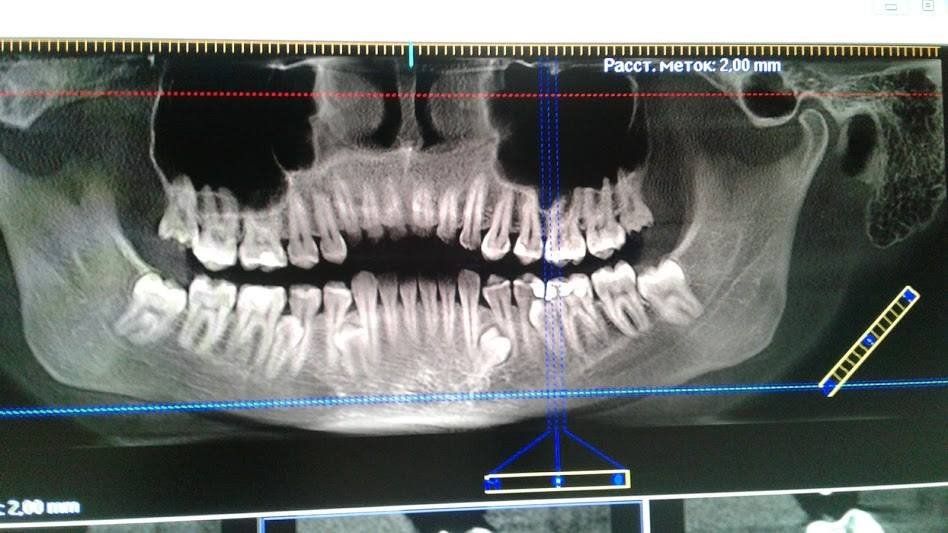

Додаткові корінні зуби – це рідкісна природна аномалія, підтверджена рентгенівськими знімками і висновками фахівців. Таких власників «надкомплектів зубів» на планеті всього 3%. Мешканка Світловодська Юлія Фоміна трохи не дотягла до світового рекорду – у самої «зубастої» людини на планеті 37 зубів.